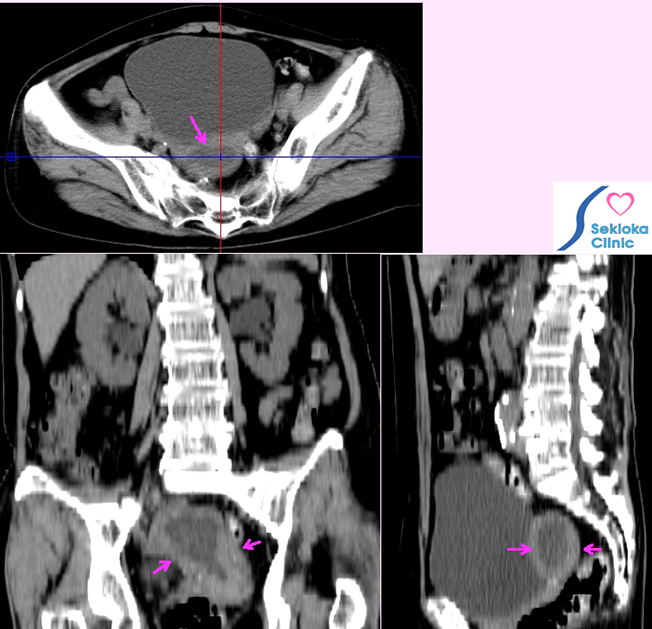

子宮体部がん

自覚症状

なし、その後不正出血

診断

原因不明の胸水と微熱で検査、偶然認められた。

治療

子宮摘出